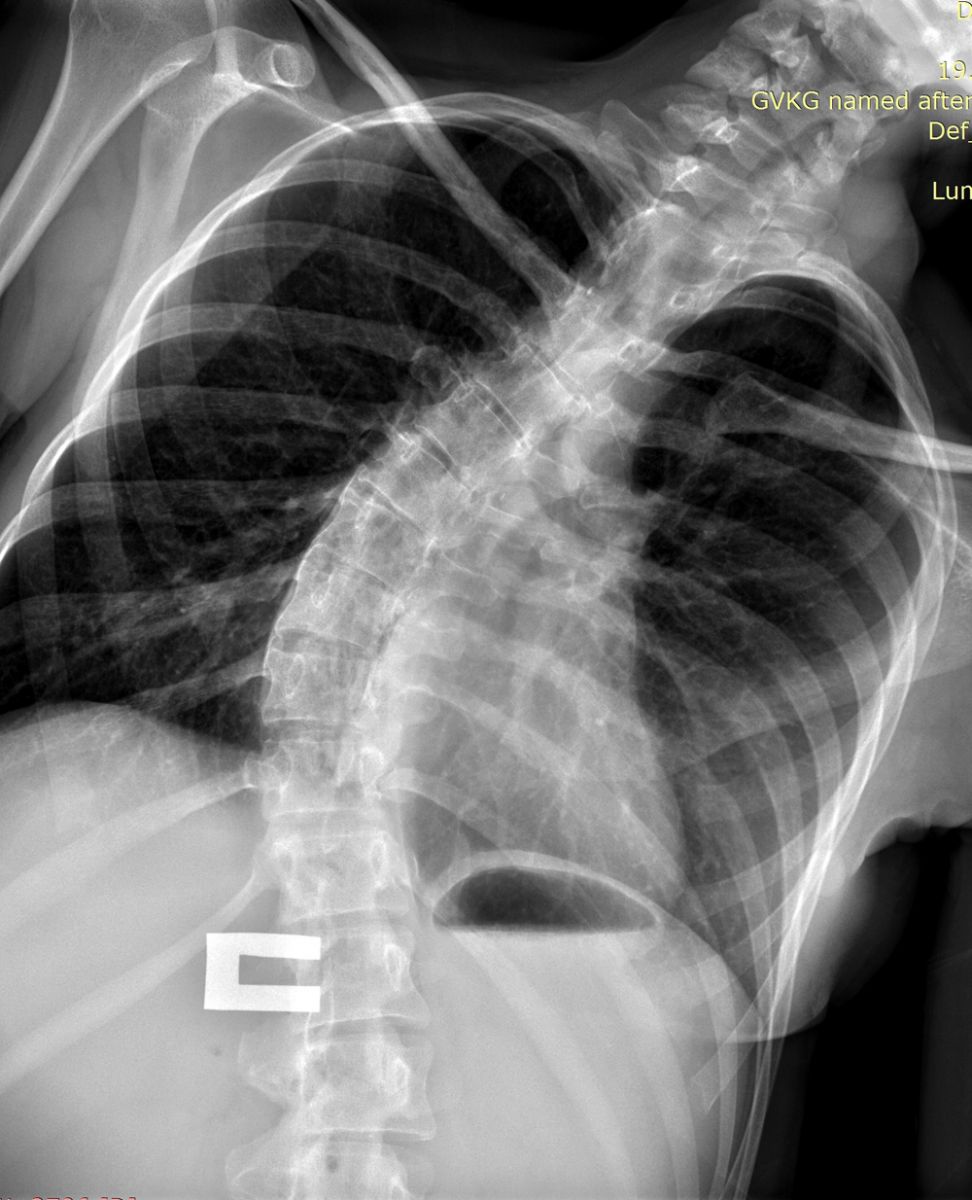

Рис - КТ Сколиоз

На этапе планирования обязательно выполняют (постуральные) рентгенограммы в двух проекциях (сбоку и спереди), при котором снимок захватывает весь позвоночник. Также необходимы (функциональные) снимки с наклонами в сторону. Если на таких снимках позвоночный столб плохо выравнивается, то деформацию считают ригидной.

Рис - Сколиоз